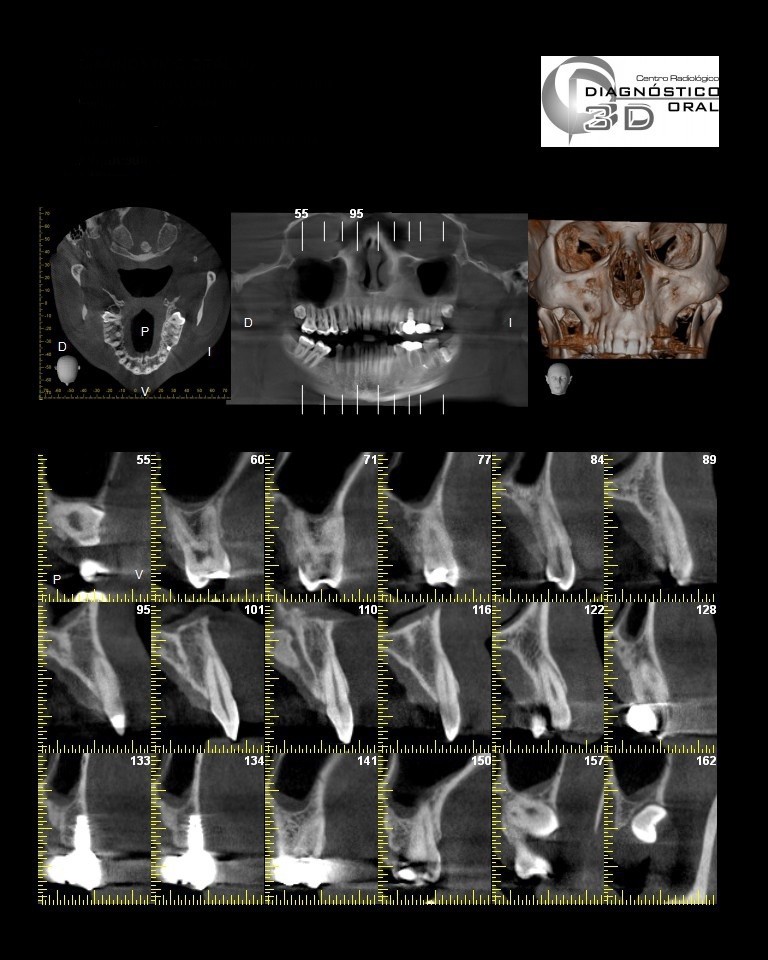

El Centro Radiológico Diagnóstico Oral 3D, es una empresa antioqueña que ofrece a sus pacientes desde el año 2009, tecnología de vanguardia en radiografías tridimensionales con calidad fotográfica. Las posibilidades para mejorar la eficacia en los diagnósticos bucales son evidentes, también lo son las posibilidades de manipulación de imagen. El sistema de imágenes en 3D ofrece detalles sin precedentes, convirtiéndola en la opción idónea para la mayoría de aplicaciones odontológicas, incluyendo implantes, tratamiento de conductos, ortodoncia, odontopediatría, periodoncia y cirugía

El mayor beneficiado con el uso de esta tecnología es el paciente, el cual podrá ser evaluado en todas sus dimensiones con una baja dosis de radiación, con un costo accesible y sin contaminar  el medio ambiente. Dependiendo de la necesidad del paciente, hay varios tipos de tomografías y los especialistas en el área odontológica hacen uso de ellas según su especialidad.

Evaluación de patologías dentales y maxilofaciales

Planificación de tratamientos ortodónticos y ortognáticos

Implantología dental